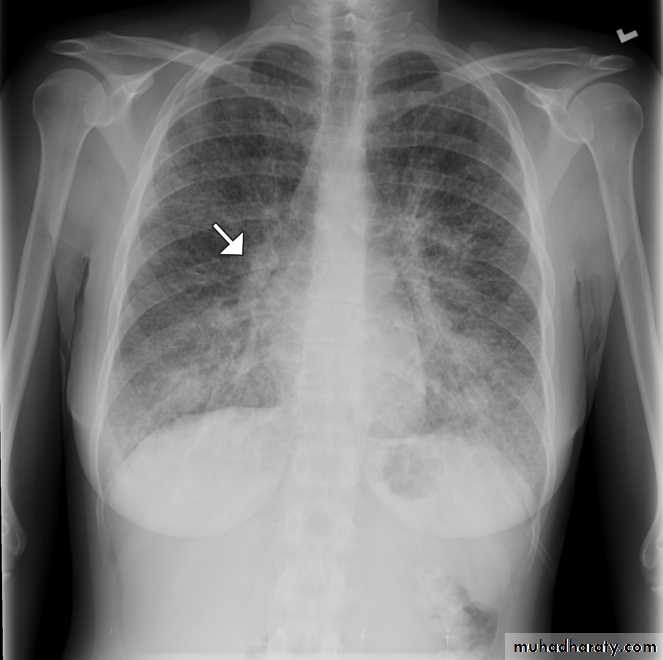

Chest radiography of a 31-year-old woman showing diffuse interstitial and septal thickening (arrow) in both lungs.